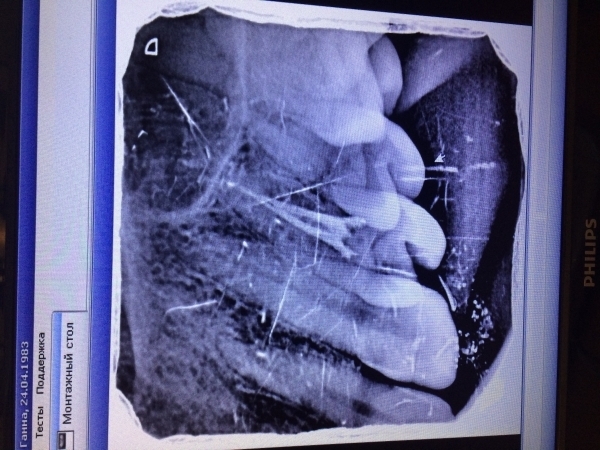

В феврале лечили верхнюю четверку слева, почистили полость и поставили пломбу. К вечеру зуб прострелило, появилось онемение и периодическая боль. Принято решение депульпировать. Все симптомы сразу исчезли. Неделю ходила с кальцием в каналах, в марте поставили постоянную пломбу. Месяц зуб практически никак не беспокоил, было ощущение чего-то инородного. Через месяц внезапно появилась боль и онемение по всем зубам слева сверху, но потом локализовалось в области четверки. На рентгене изменений нет. Боль усиливается, если появляется онемение, боль стихает. Субъективно, зуб кажется подвижным, хотя стоматолог это отрицает и утверждает, что с зубом все нормально. Зуб как будто в заморозке, есть отечность щеки и сглаженность носогубной складки. Невропатолог со своей стороны говорит о вторичной патологии, вызванной зубом. Сделала КТ, стоматолог утверждает, что все с зубом нормально.